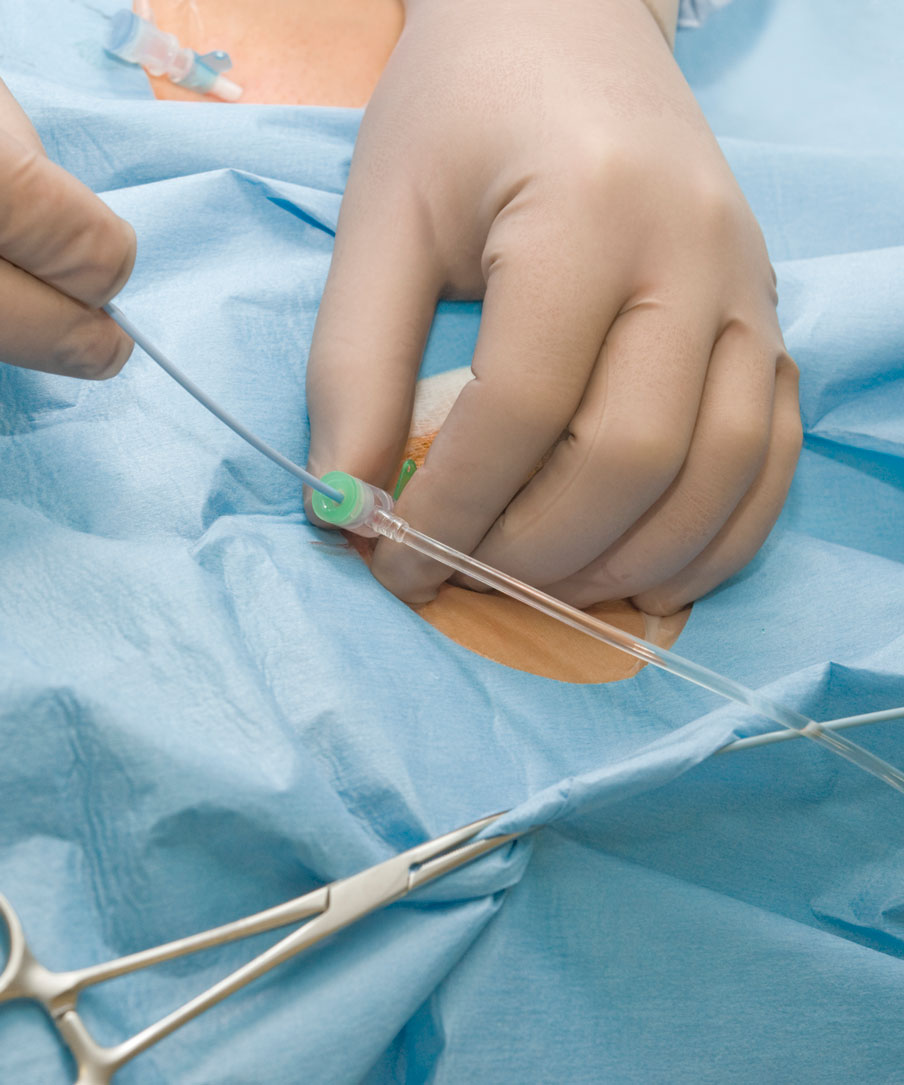

Хирургические процессы при эмболизации гемангиомы на фото

Раздел: Снимки-откровения